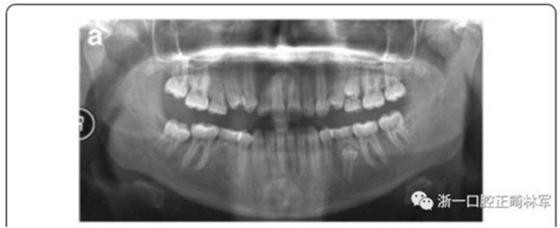

上下頜右側(cè)第二乳磨牙存,其余乳磨牙已脫落;

影像學檢查,右側(cè)第二前磨牙和所有第三磨牙先天性缺失;